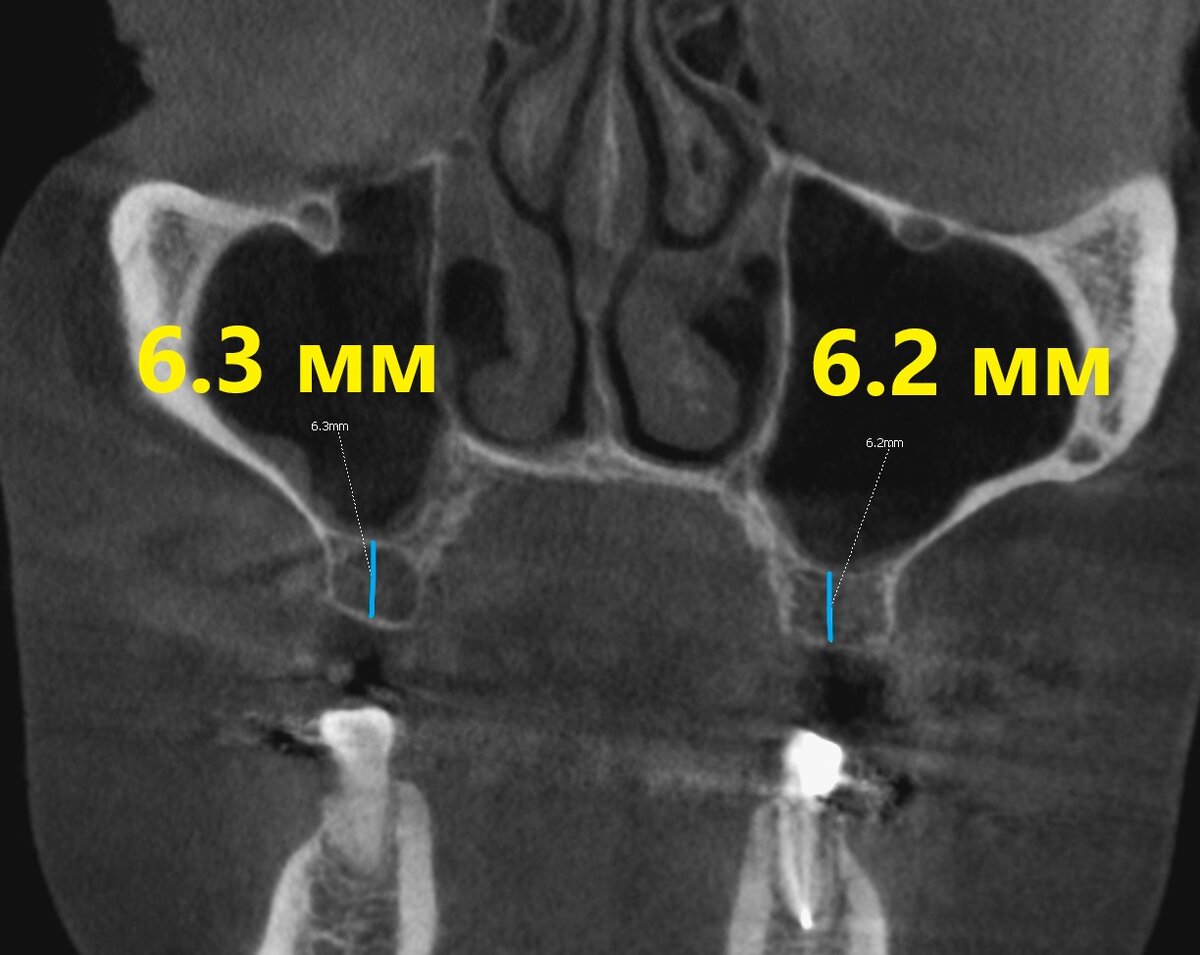

Посмотрим на снимок КЛКТ до:

Перед синус-лифтингом

Кость, вроде бы, есть. Но для полноценных имплантатов её недостаточно.

Да, можно установить агрессивные короткие с широкими лопастями - но мы, так уж повелось, как-то за проверенные классические методы там, где их можно применить спокойно.

Для открытого синус-лифтинга такой объём собственной кости - как-то жирно. Поэтому пойдём другим путём.